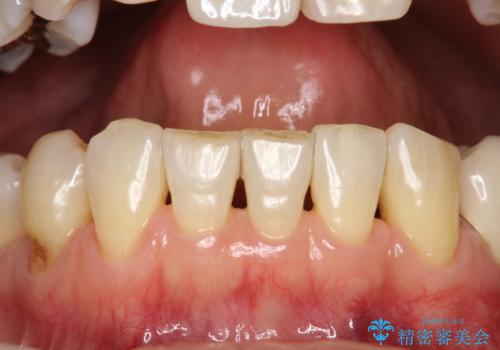

- 定期的にメンテナンスにいらしている方です。特にお変わりないとのことでPMTC60分コースで全体的なクリーニングを行いました。